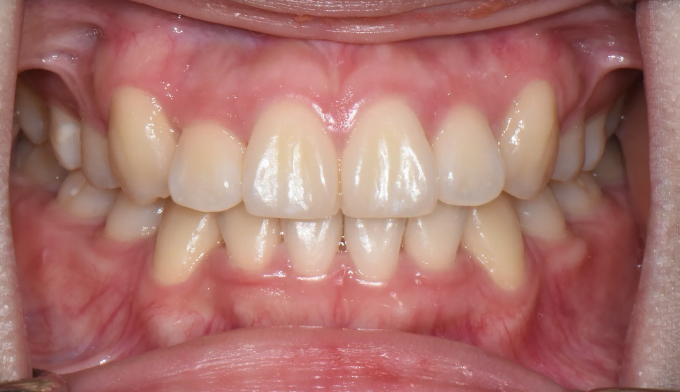

돌출입 정도는 약하지만, 공간이 매우 부족하여 덧니가 명확한 케이스 입니다.

치아 배열을 위한 공간이 많이 필요하기 때문에 발치를 통하여 공간을 먼저 확보하였습니다.

발치가 필요한 경우, 일반적으로 덧니인 송곳니보다는 작은어금니를 발치합니다. 가장 쓰임이 적고 덜 중요한 치아이기 때문입니다. 하지만 발치치아는 사람마다 그리고 케이스마다 달라집니다.

가지런한 치열을 갖기까지의 교정기간은 21개월 이었습니다.